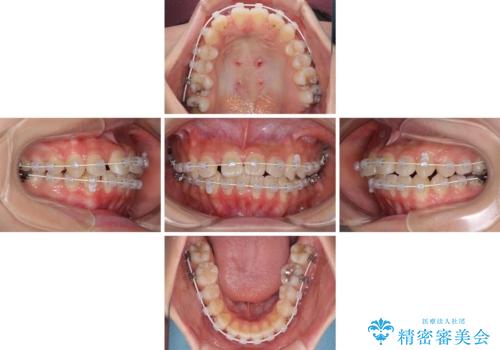

急速拡大装置で狭い歯列を骨格ごと改善 ワイヤー装置による矯正治療

- 下顎の前突感と前歯の叢生を気にして来院された患者様です。

下顎前方位の骨格のため、下顎歯列に対して上顎歯列の幅が狭くなっていました。

急速拡大装置を用いて上顎骨を側方に拡大し、上顎の叢生を解消するとともに下顎歯列拡大により下顎の叢生も解消することとしました。

急速拡大装置使用直後は著しいスペースが正中に発現するため、ワイヤー矯正を行いますが、今回は治療期間を短くしたいとのことで、上下全体をワイヤー装置にて矯正治療することとしました。